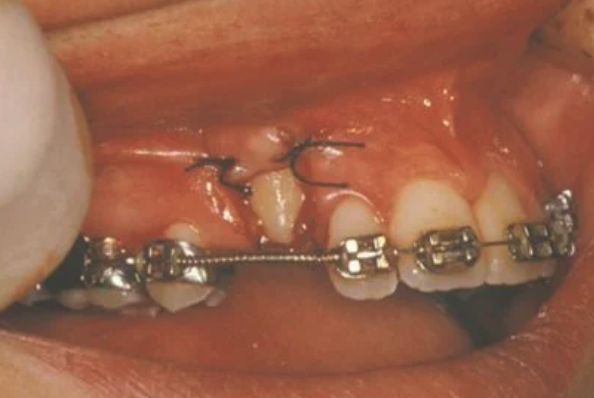

In cases where the eyeteeth will not erupt spontaneously, the orthodontist and oral surgeon will work together to get these teeth to erupt. Each case must be evaluated on an individual basis, but treatment will usually involve a combined effort between the orthodontist and the oral surgeon. The oral surgeon will expose and bracket the impacted eyetooth.

The goal is to erupt the impacted tooth and not to extract it. Once the tooth has moved into its final position, the gum around it will be evaluated. In some circumstances, there may be some minor “gum surgery” required.